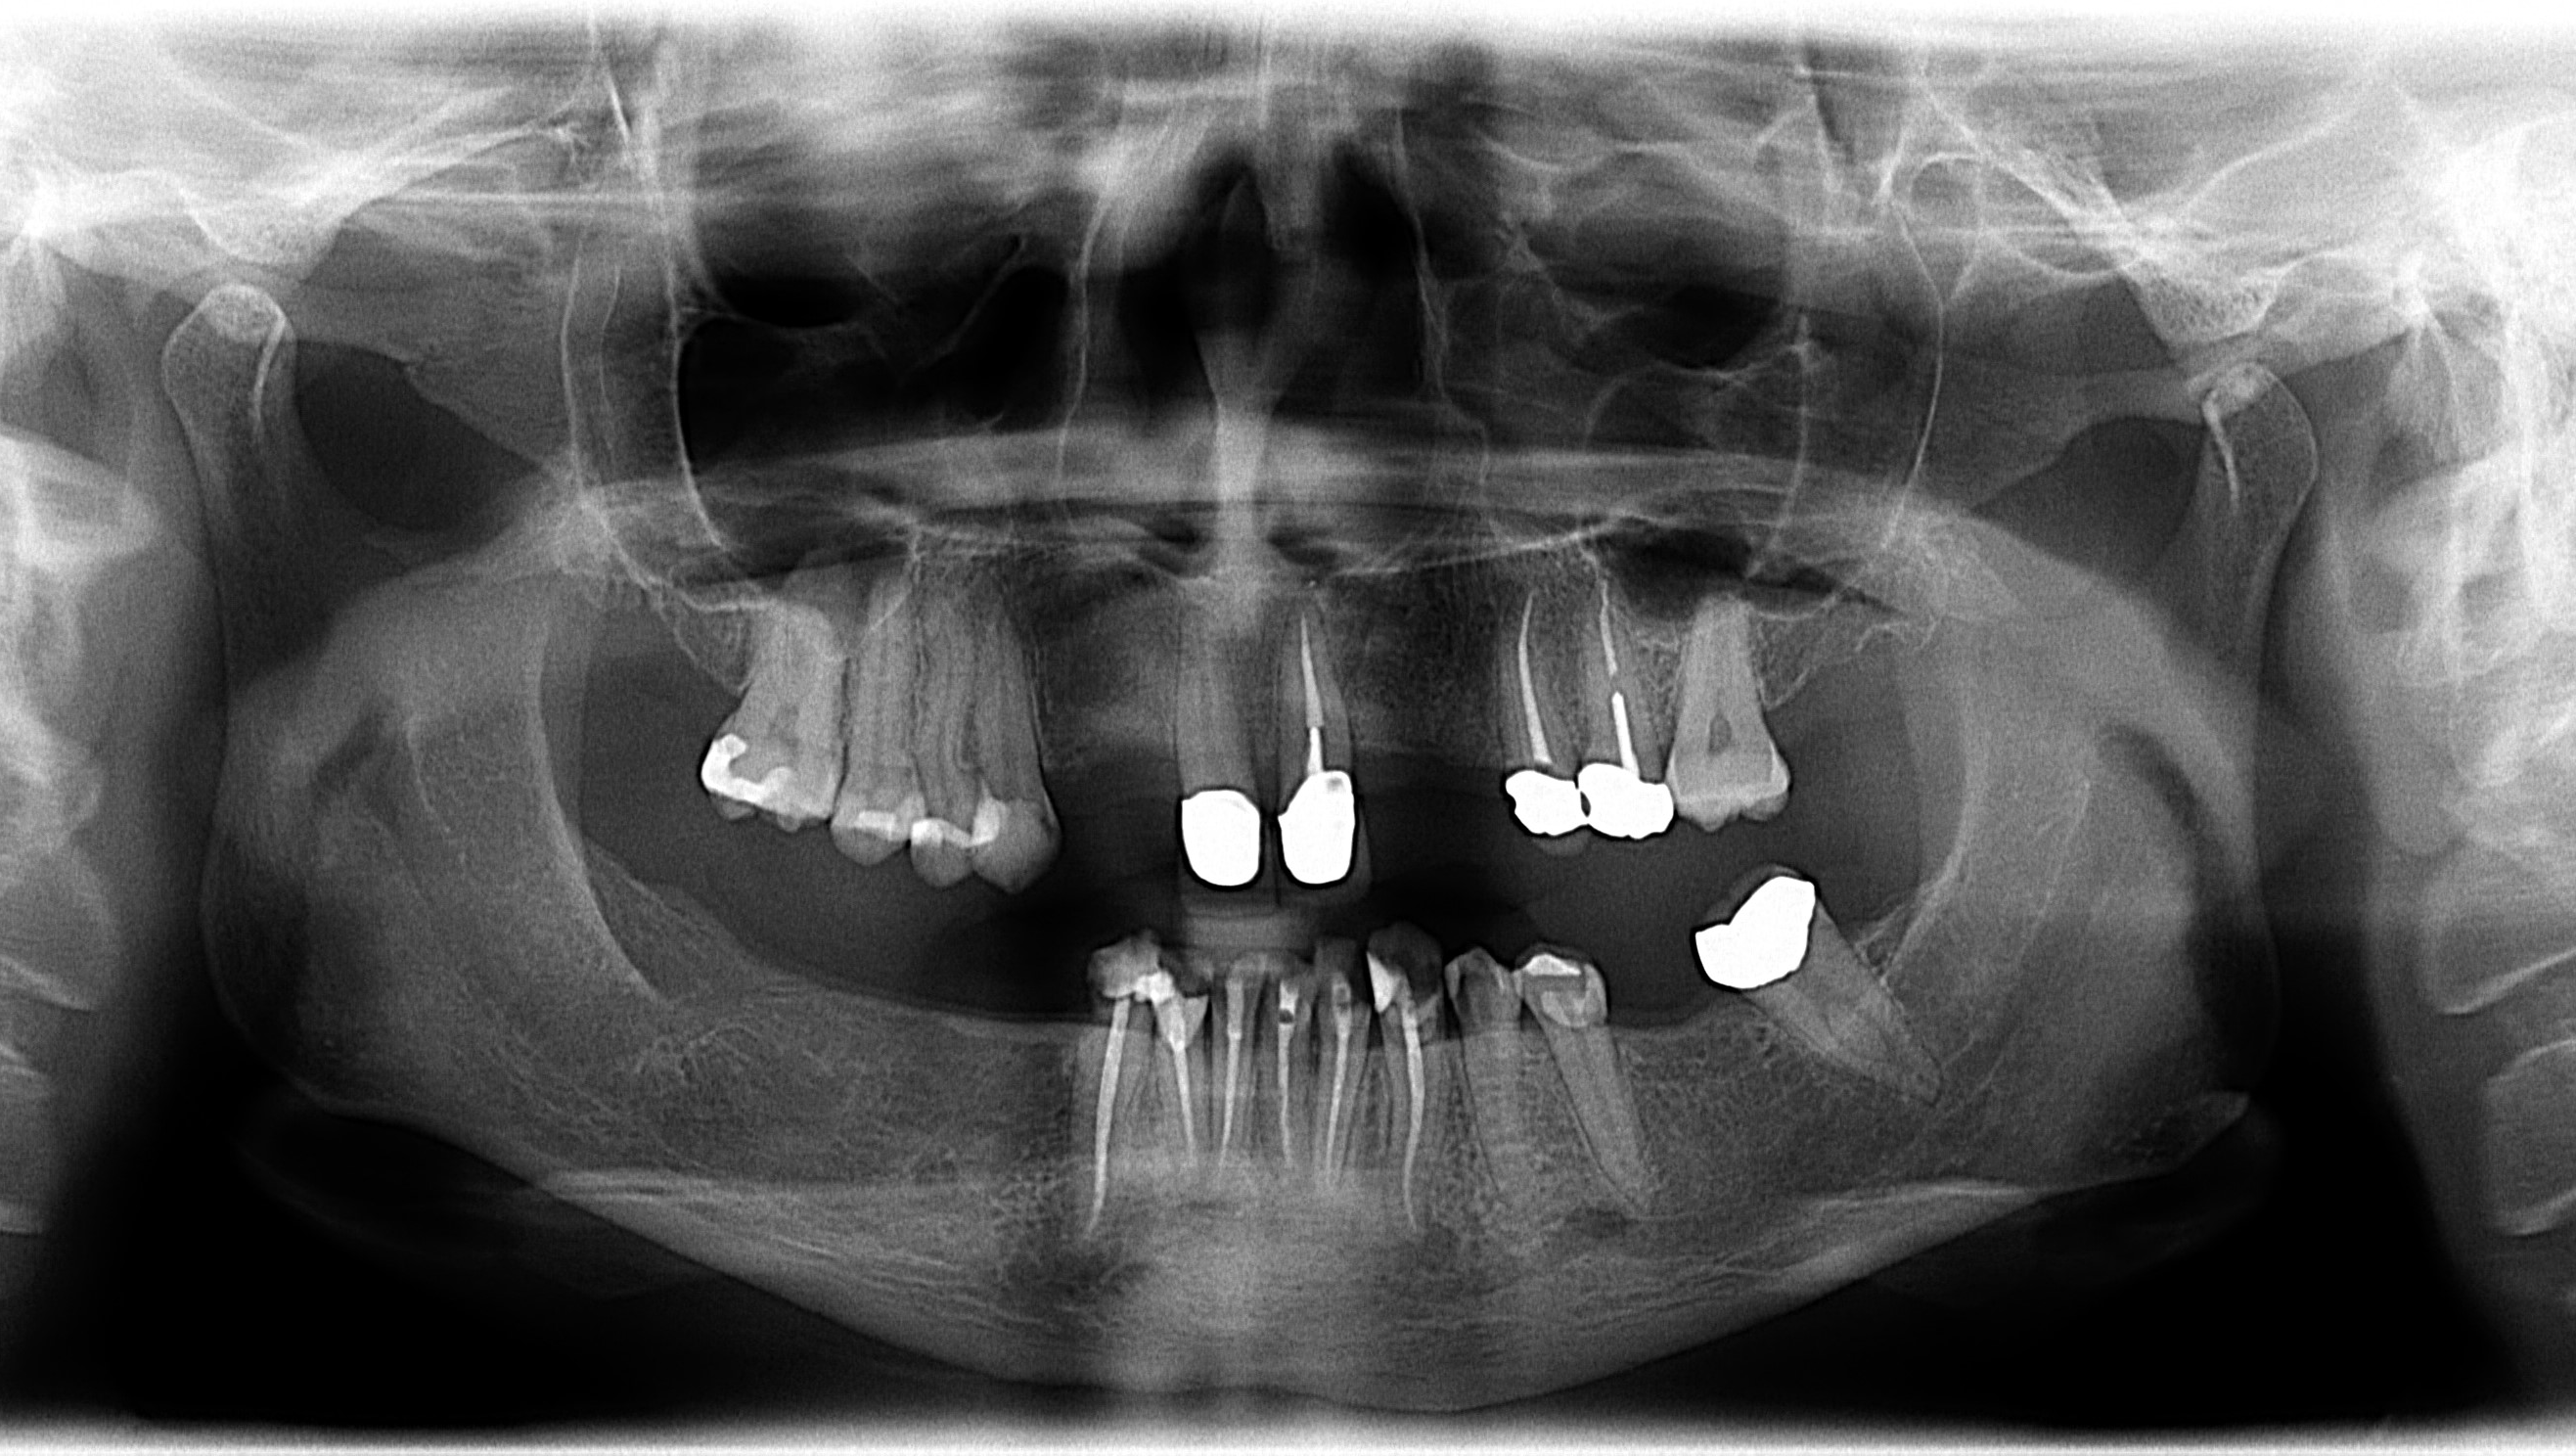

In my case, lack of care was not the only issue. I was born without several of my adult teeth. One of my teeth decided to grow sideways inside my jaw, which necessitated surgery to remove. My top front teeth are off-center as a result. I have soft enamel, periodontal disease, and bone loss in my jaw. Because of the high costs of care, whenever I would develop a problem, the cheapest solution was to just pull the tooth. Not ideal, but when you’re in an extreme amount of pain from an abscess bad enough to stop a human heart, you’ll do what you must do to make it stop.

I have sixteen teeth remaining. I am now unable to chew properly and have almost stopped eating solid food entirely. I am rapidly losing weight, and my mouth hurts all the time, every day. I wake up in pain and go to bed in pain. Eating hurts every single time. Sometimes my gums are so inflamed I can’t even drink or swallow. I struggle with multiple infections a year, and it’s almost certain my teeth are the source of my chronic migraines.

If you made it this far, bless you. I will continue to upload more information as I obtain it—for one thing, I have the estimates for care by local dentists, I have photos, x-rays, and coming soon: video. I will also interview my friends so you can get an idea of who I am as an individual, in the interest of full transparency. If this fundraiser is successful, I will then use it to document my dental journey and provide receipts as the work is completed.